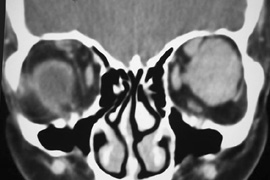

Fig. 25. A,B. Coronal (A) and axial (B) CT scans demonstrating well-encapsulated mass posteriorly in the superonasal orbit. An excellent alternative to transcranial orbitotomy for this lesion is an anterior approach via a vertical-lid splitting incision.

Procedure